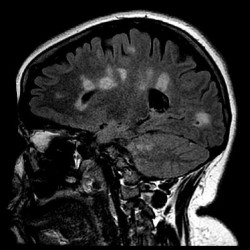

La falta de vitamina D provoca demencia, según un estudio

La demencia es una de las principales causas de discapacidad y dependencia entre las personas mayores de todo el mundo, y afecta al pensamiento y al comportamiento a medida que se envejece. Pero, ¿y si se pudiera frenar esta enfermedad degenerativa en seco? Ahora, un pionero estudio genético de la Universidad del Sur de Australia ha mostrado una relación directa entre la demencia y la falta de vitamina D.